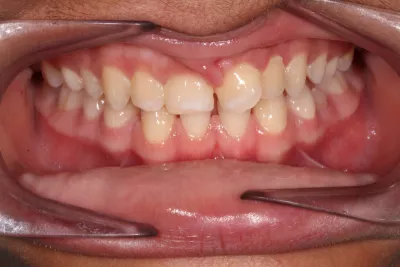

Invisalign & Teeth Whitening

6 months Invisalign & Teeth Whitening